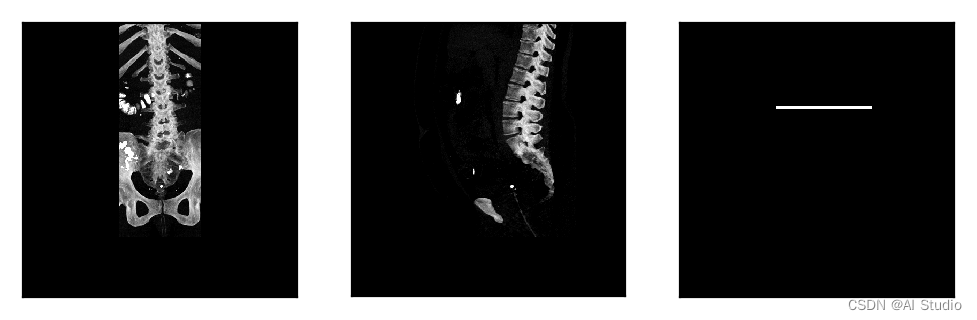

对读取数据集进行展示。

images_frontal_ = np.squeeze(images_frontal_[0,:,:])

images_sagittal_ = np.squeeze(images_sagittal_[0,:,:])

label = np.squeeze(label)

imga = Image.fromarray(images_frontal_*255)

imgb = Image.fromarray(images_sagittal_*255)

imgc = Image.fromarray(label*255)

plt.figure(figsize=(6, 2))

plt.subplot(1,3,1),plt.xticks([]),plt.yticks([]),plt.imshow(imga)

plt.subplot(1,3,2),plt.xticks([]),plt.yticks([]),plt.imshow(imgb)

plt.subplot(1,3,3),plt.xticks([]),plt.yticks([]),plt.imshow(imgc)

plt.show()